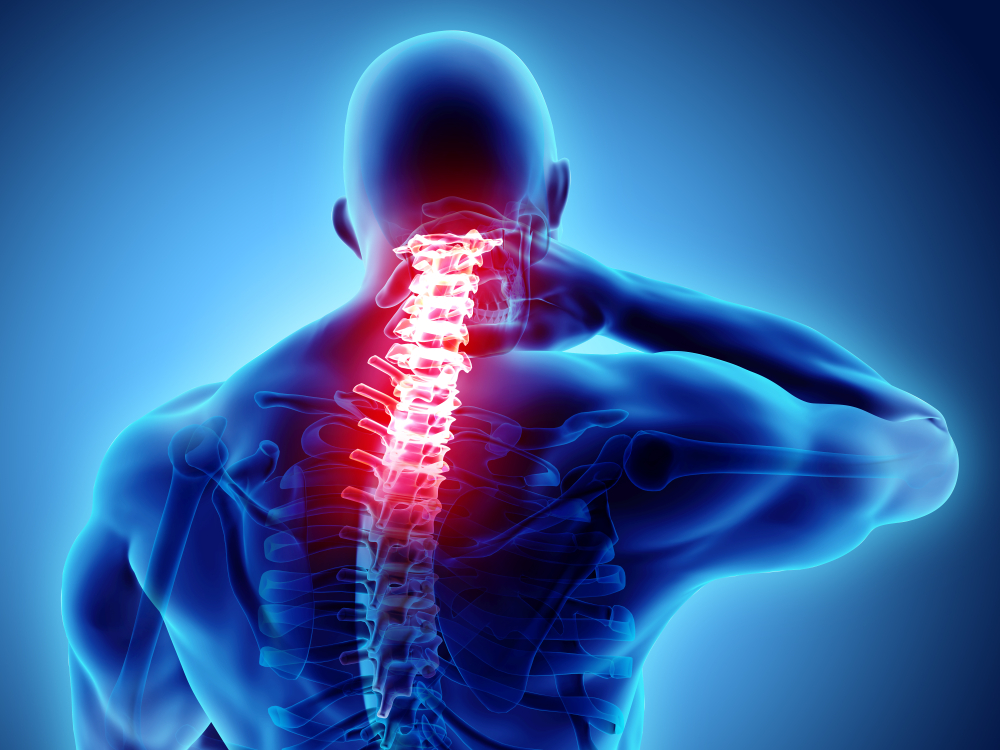

Natural treatment for cervical pain and stiffness using Ayurvedic herbs and therapies.

Specialized Ayurvedic therapies to treat spinal disorders and strengthen the spine.